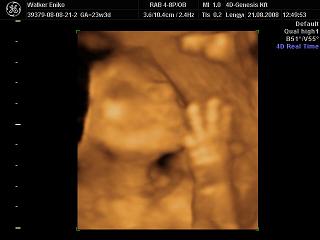

Nagyon helyesek a 4D-s fotók!!!